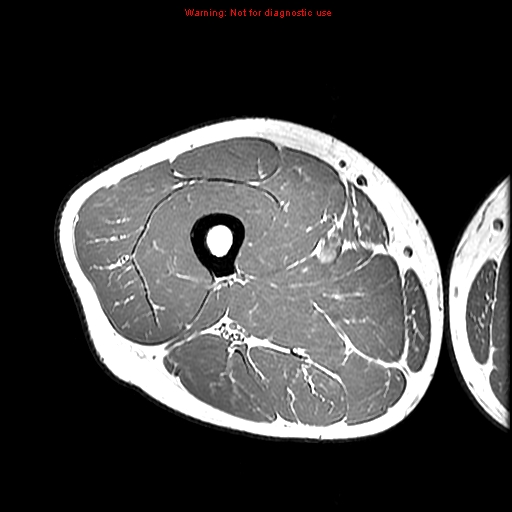

gracilis muscle rectus femoris

rectus femoris

sartorius muscle rectus femoris

vastus intermedius

vastus lateralis

sciatic nerve

gluteus maximus

biceps femoris (long head)

semitendinosus muscle

adductor magnus vastus lateralis

tibial nerve

common fibular nerve

femoral artery

biceps femoris (short head)

semitendinosus

semimembranosus

adductor magnus

vastus medialis muscle

vastus medialis muscle rectus femoris

sartorius muscle

sartorius muscle popliteal artery

popliteal artery